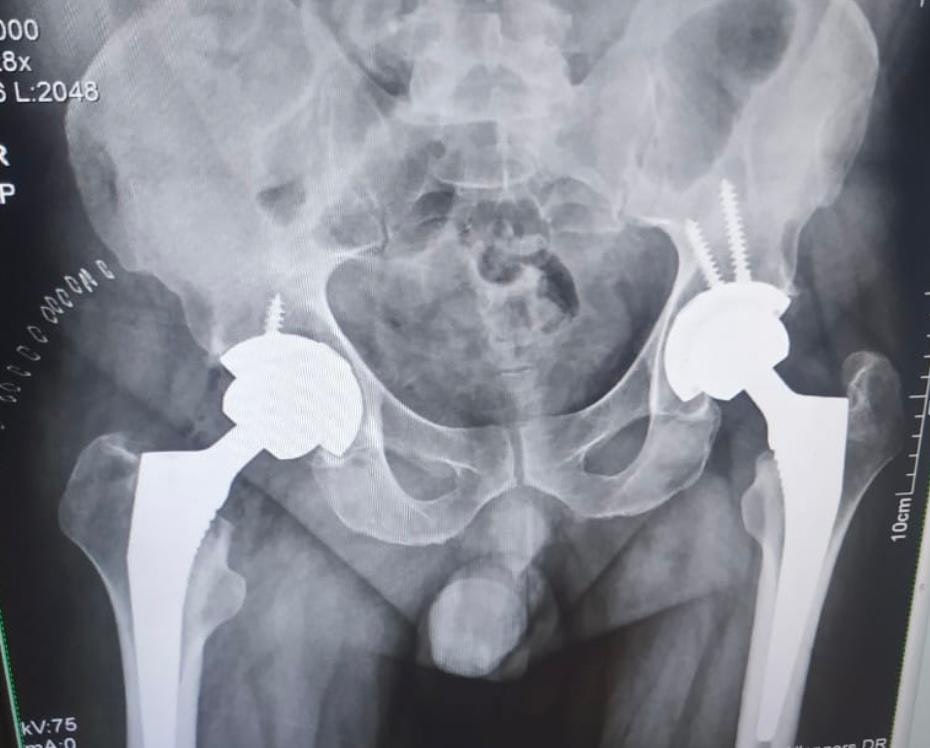

Best Surgeon for Total Hip Replacement in Mohali

Dr. Vikramjit Singh Baath | ORTHOPRO – Expert Total Hip Replacement Surgeon in Mohali

Dr. Baath performs total hip replacement surgeries using modern implants and minimally invasive methods to relieve pain and enhance mobility for patients with hip arthritis and joint damage.